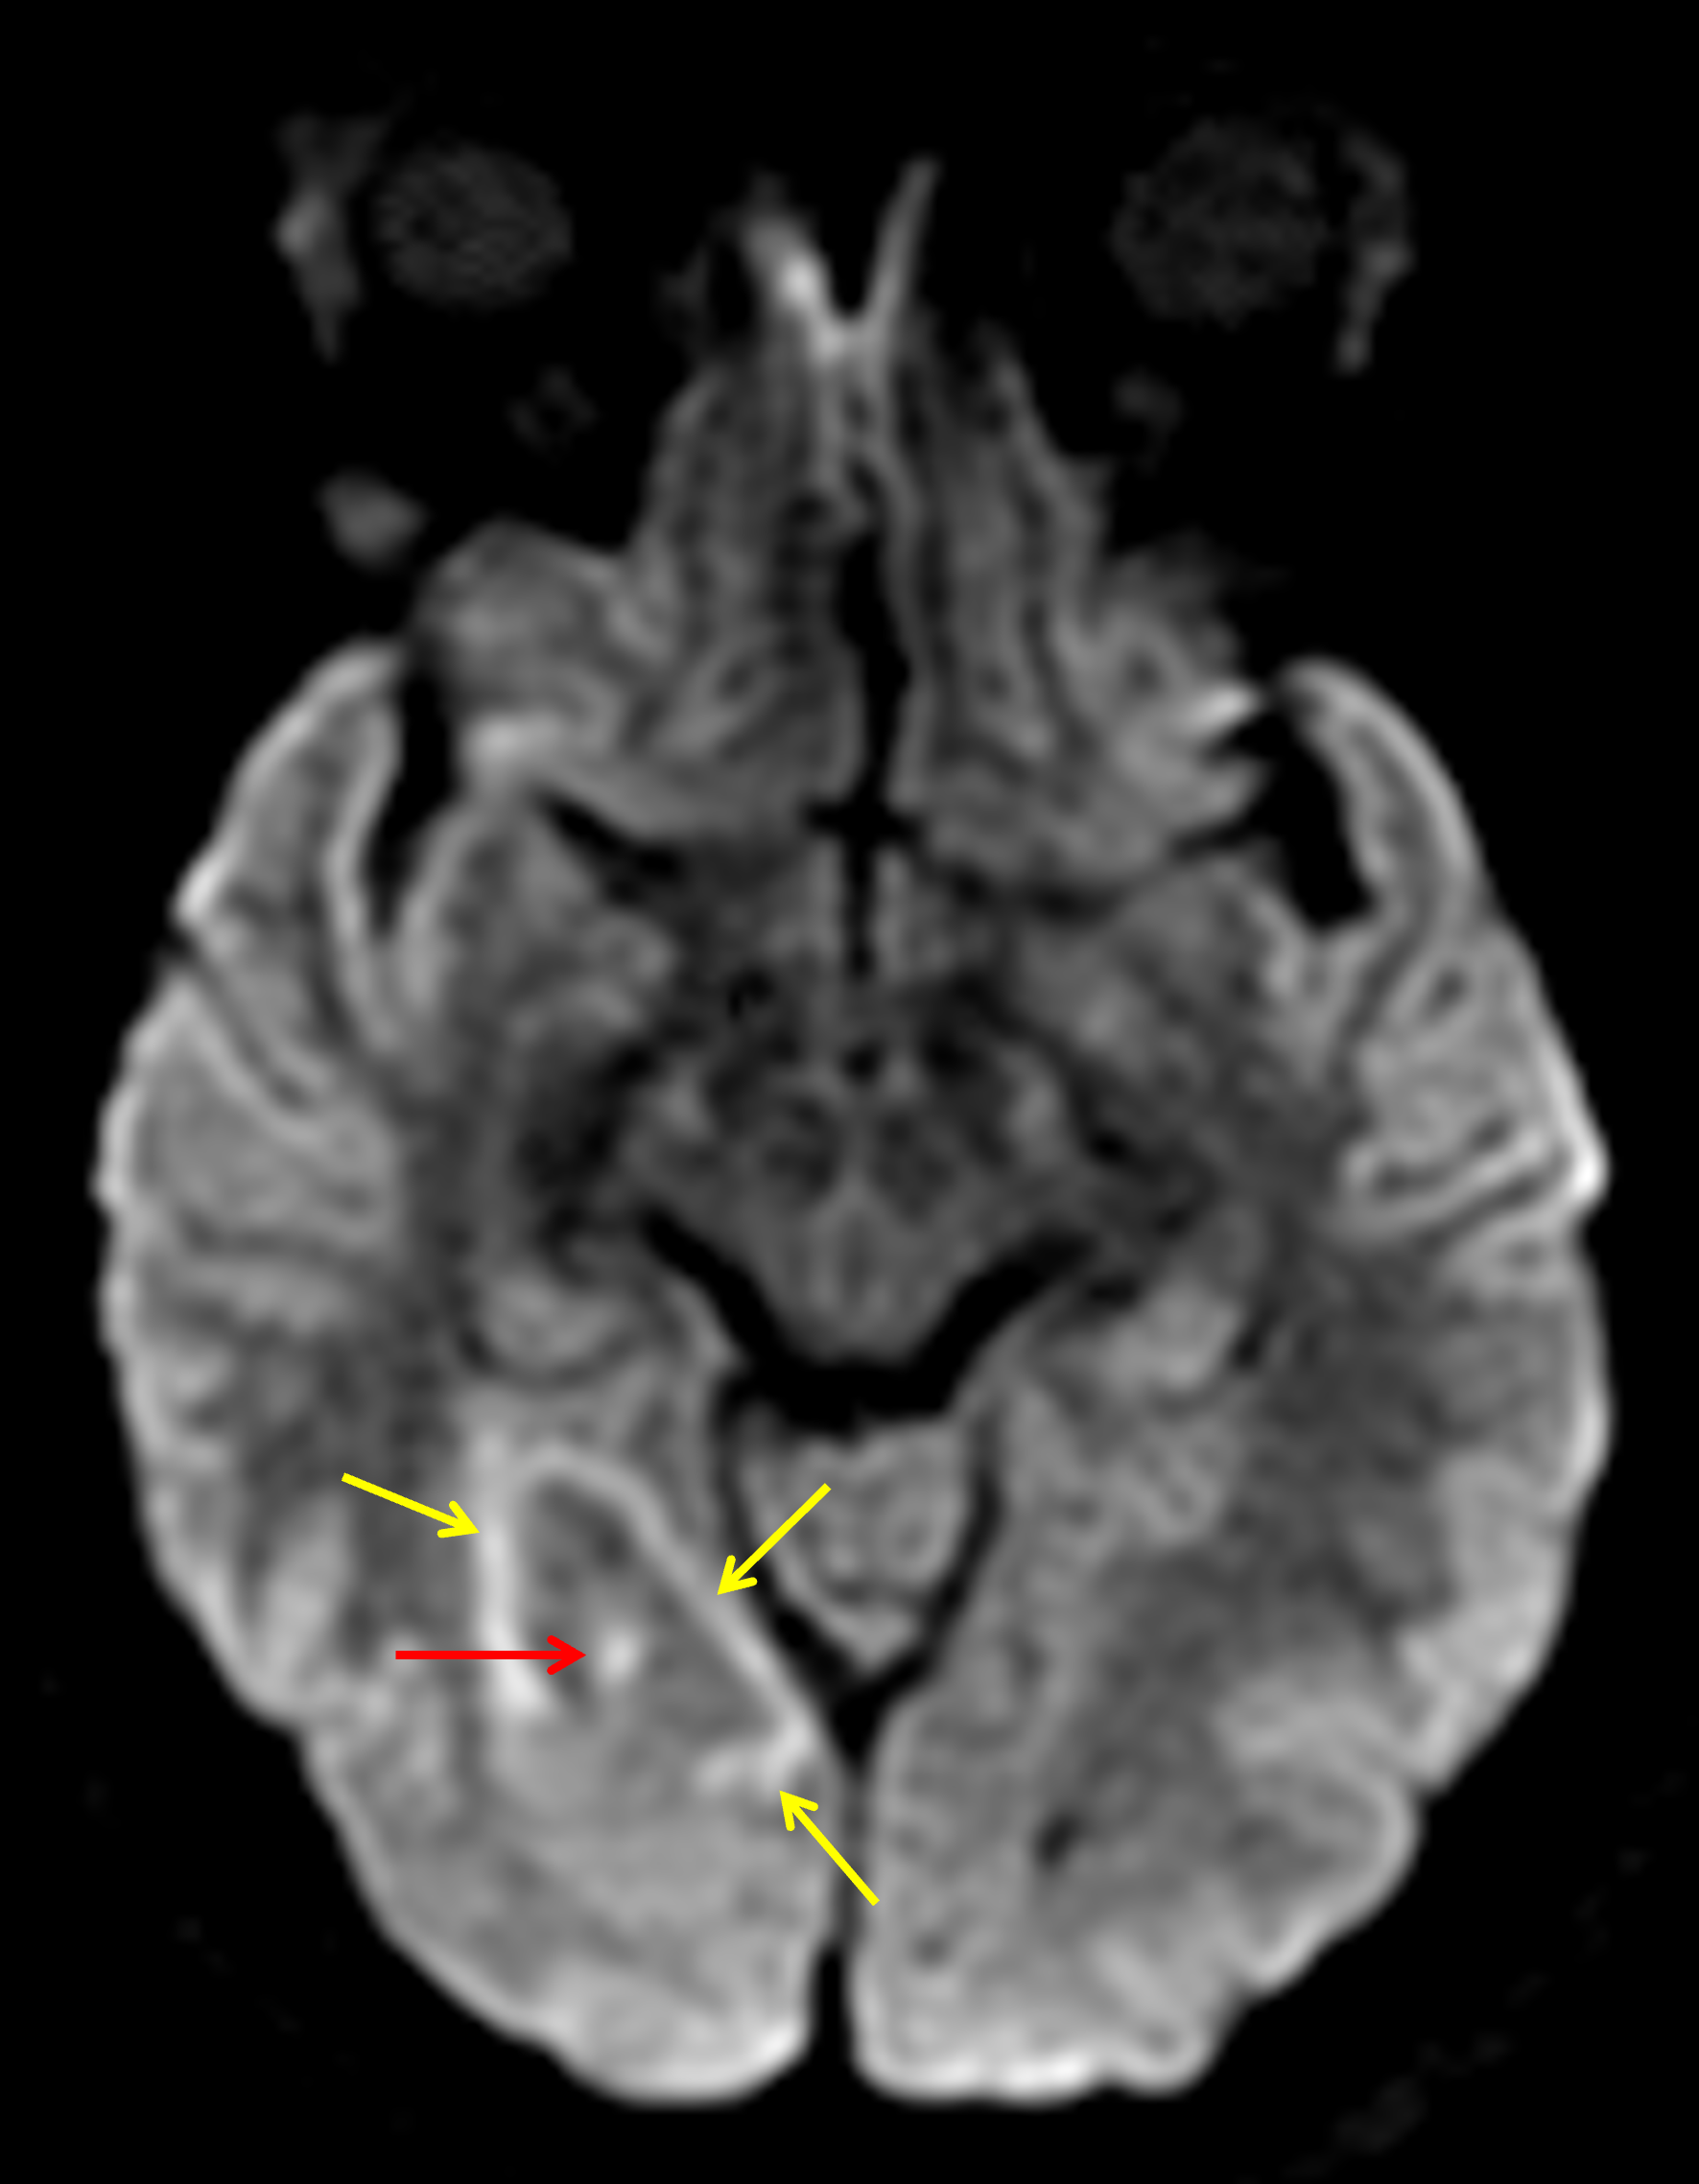

Age: 34

Sex: Female

Indication: Headache, history of HIV/AIDS

CNS toxoplasmosis